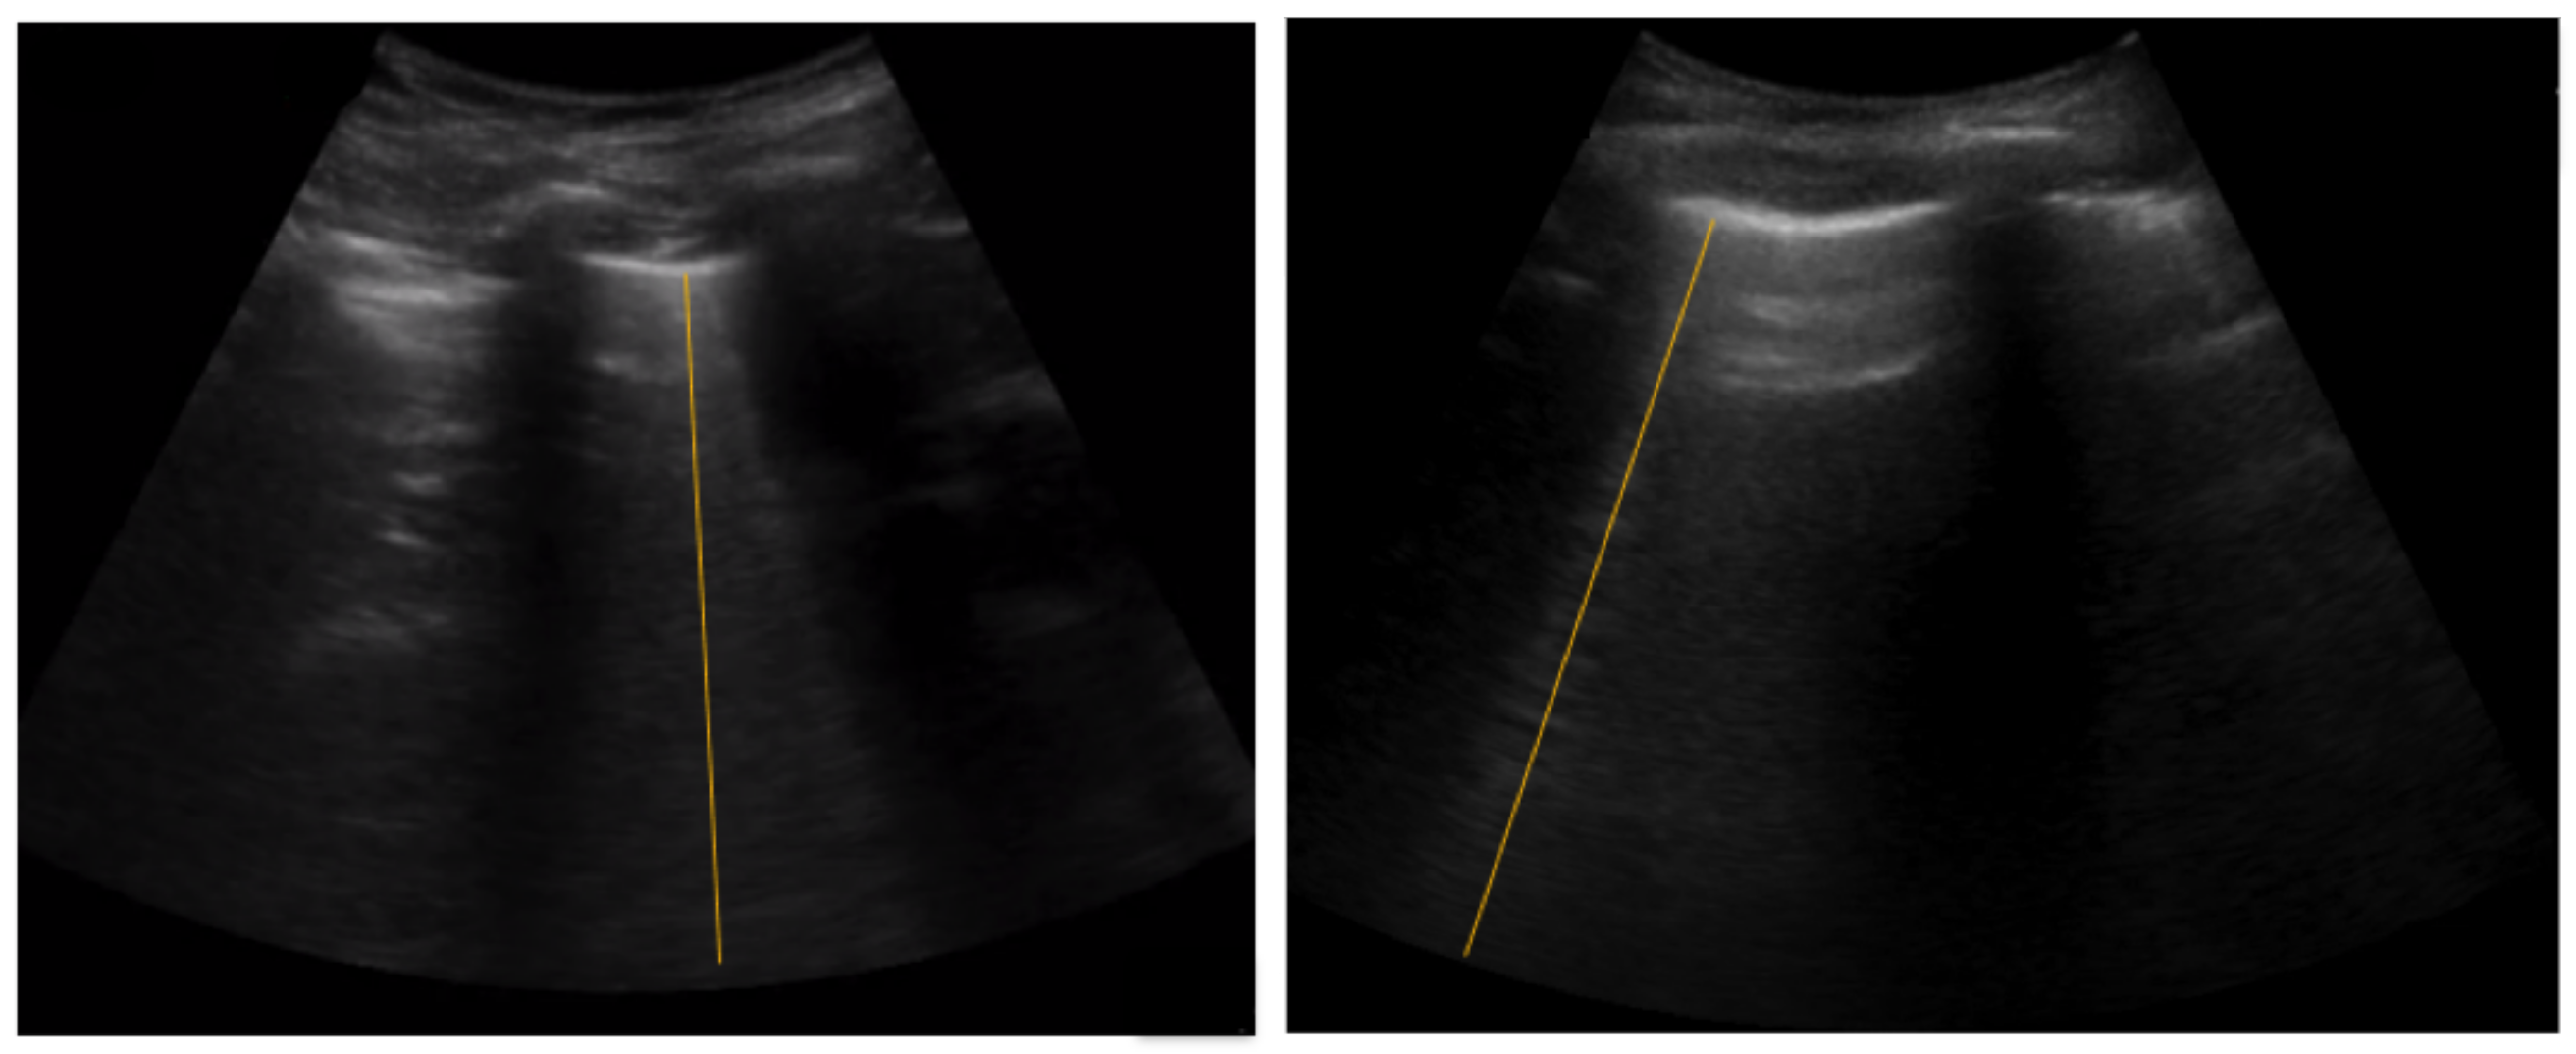

5.2. Spatial B-Line Localization

3.2. Spatial Attention Mechanism